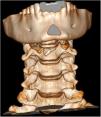

En la valoración, refiere dolor cervical y odinofagia. En la exploración se objetiva un hematoma cervical anterior. Se realiza una radiografía cervical para descartar lesiones de la vía aérea, identificando una lesión compatible con fractura de hioides (fig. 1). Se confirma el diagnóstico de fractura-luxación del asta mayor izquierda del hueso hioides mediante TC, descartando lesiones asociadas (figs. 2 y 3). Se decide tratamiento conservador con analgesia, dieta semiblanda y corticoterapia. Se realiza una laringoscopia que descarta complicaciones. Dada la buena evolución, se decide alta a las 24 h.